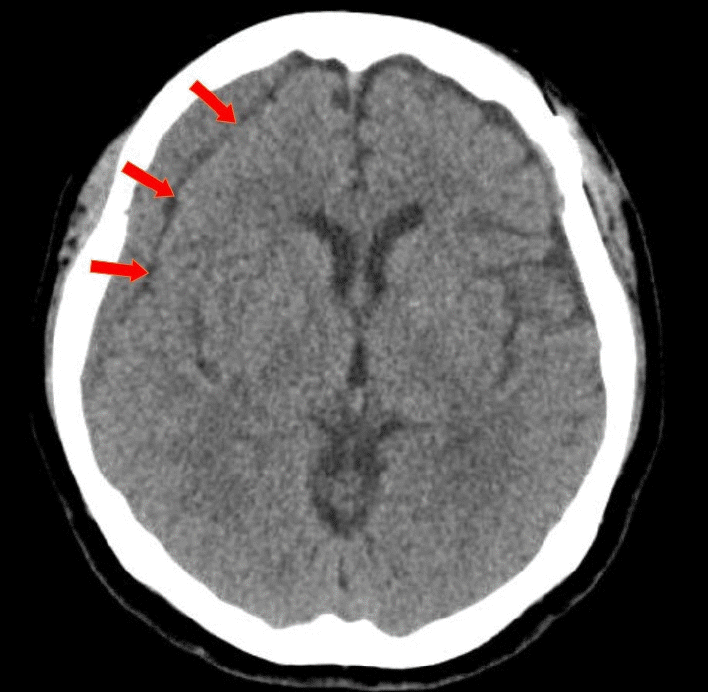

To measure the volume of the subdural hematoma, volumetric studies were performed using the axial planes of the CT scan with a section thickness of 5 mm. PiViewSTAR (Infinitt Co., Ltd., Seoul, Korea), a picture archiving and communication system (PACS), was used to measure the area of the subdural hematoma in each axial slice by manually outlining the region of interest. The maximum midline shift was measured as the maximum length of deviation from the vertical midline of the skull to the septum pellucidum. Mean Hounsfield units were measured using the average figure in the single axial section of CT images, which showed the maximal thickness of CR-CSDH between the outer margin of the cortex and the inner table of the skull. The characteristics of CR-CSDH on CT scans were classified according to Nomura et al.: (A) high-density, (B) iso-density, (C) low-density, (D) mixed-density, and (E) layering [15]. And according to Nomura et al., as mixed-density and layering CSDH indicate recent bleeding, characteristics of CR-CSDH is divided into two group: homogenous-type (A, B, C) and heterogenous-type (D, E). The presence of a linear low-density area between the inner membrane of the hematoma and the outer margin of the cortex which suggesting remained CSF beneath the hematoma (Fig. 2), as reported by Hiroshi et al., was analyzed in the axial plane of the CT scan [4].

Some case examples have reported the radiologic characteristics of spontaneously resolved CSDH. Horikoshi et al. reported radiological findings of spontaneously absorbed CSDH and suggested simultaneous reduction of the hematoma and HU, hematoma in the frontal region, and linear low-density areas as signs of spontaneously absorbed CSDH [4]. This linear low-density area can be interpreted in two ways. The first is that the CSF flow between the hematoma and arachnoid membrane is maintained, and the second is that the hematoma volume is decreasing, which can be considered as a free space between the hematoma and the cortex.

Compared to patients with traumatic CSDH, patients with CR-CSDH undergo wide surgical arachnoid dissection, and the flow between the hematoma and arachnoid membrane is maintained afterwards. In our investigation, the presence of a linear low-density area was found to be statistically significant in the nonoperative group. Because the dissected arachnoid membrane is relatively wide than traumatic CSDH, we assume that there is a high possibility of spontaneous resolution without symptom aggravation.

Fig. 2.

Axial view of CT scan showing CSDH and linear low-density line, with a red arrow pointing to the low-density line which suggesting remained CSF beneath the hematoma. CT, computed tomography; CSDH, chronic subdural hematoma; CSF, cerebrospinal fluid